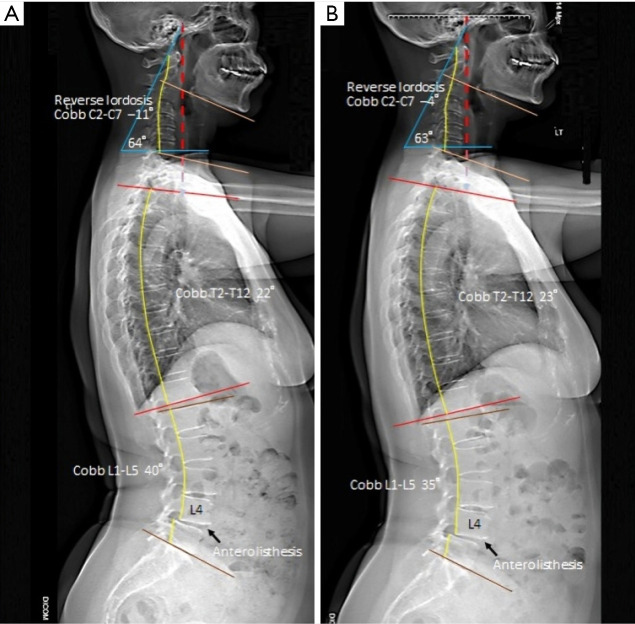

Case description: This case study involves a 60-year-old female office manager who had been suffering from neck and right shoulder pain for five years. Her family doctor diagnosed her with cervical spondylosis with cervical syndrome based on radiographic findings. She took pain medication for a year, underwent ten physiotherapy sessions and monthly massage therapy. This did not alleviate her problems, but caused her head slowly droop forward. EOS® radiography at the first chiropractic consultation showed reverse lordosis of the cervical spine, degeneration of the C4/5, C5/6, L3/4, L4/5, and L5/S1 intervertebral discs, and marginal osteophytes. A working diagnosis of age-related hyperkyphosis and cervical postural syndrome was made based on the main symptoms and clinical findings. After a 24-month multimodal chiropractic treatment program, the corrected thoracic curvature resulted in the simultaneous remission of cervical symptoms.